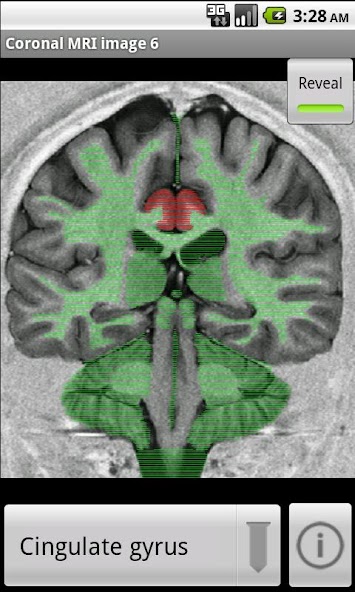

Neuroanatomy with Interactive Slices and MRI Scans of Human Brain & Spinal Cord

Learn your neuroanatomy using interactive mapped images. Each slice has neuroanatomical regions mapped out so that you can familiarise yourself with nuclei and tracts of the brain and spinal cord. I hope that NeuroSlice will be useful to training neurologists, neurosurgeons, medical students, and neuroscience students.

Neuroscan comprises 40 images taken from MRI scans and stained brain sections, which have been digitally labeled with the anatomical regions. They are all downloaded in the 6MB so you can browse offline.

1) touch a region to highlight it, and its name will be displayed

2) select the name of a region, and the region will be highlighted

3) search the database of regions to show which slices a given locus is visible.